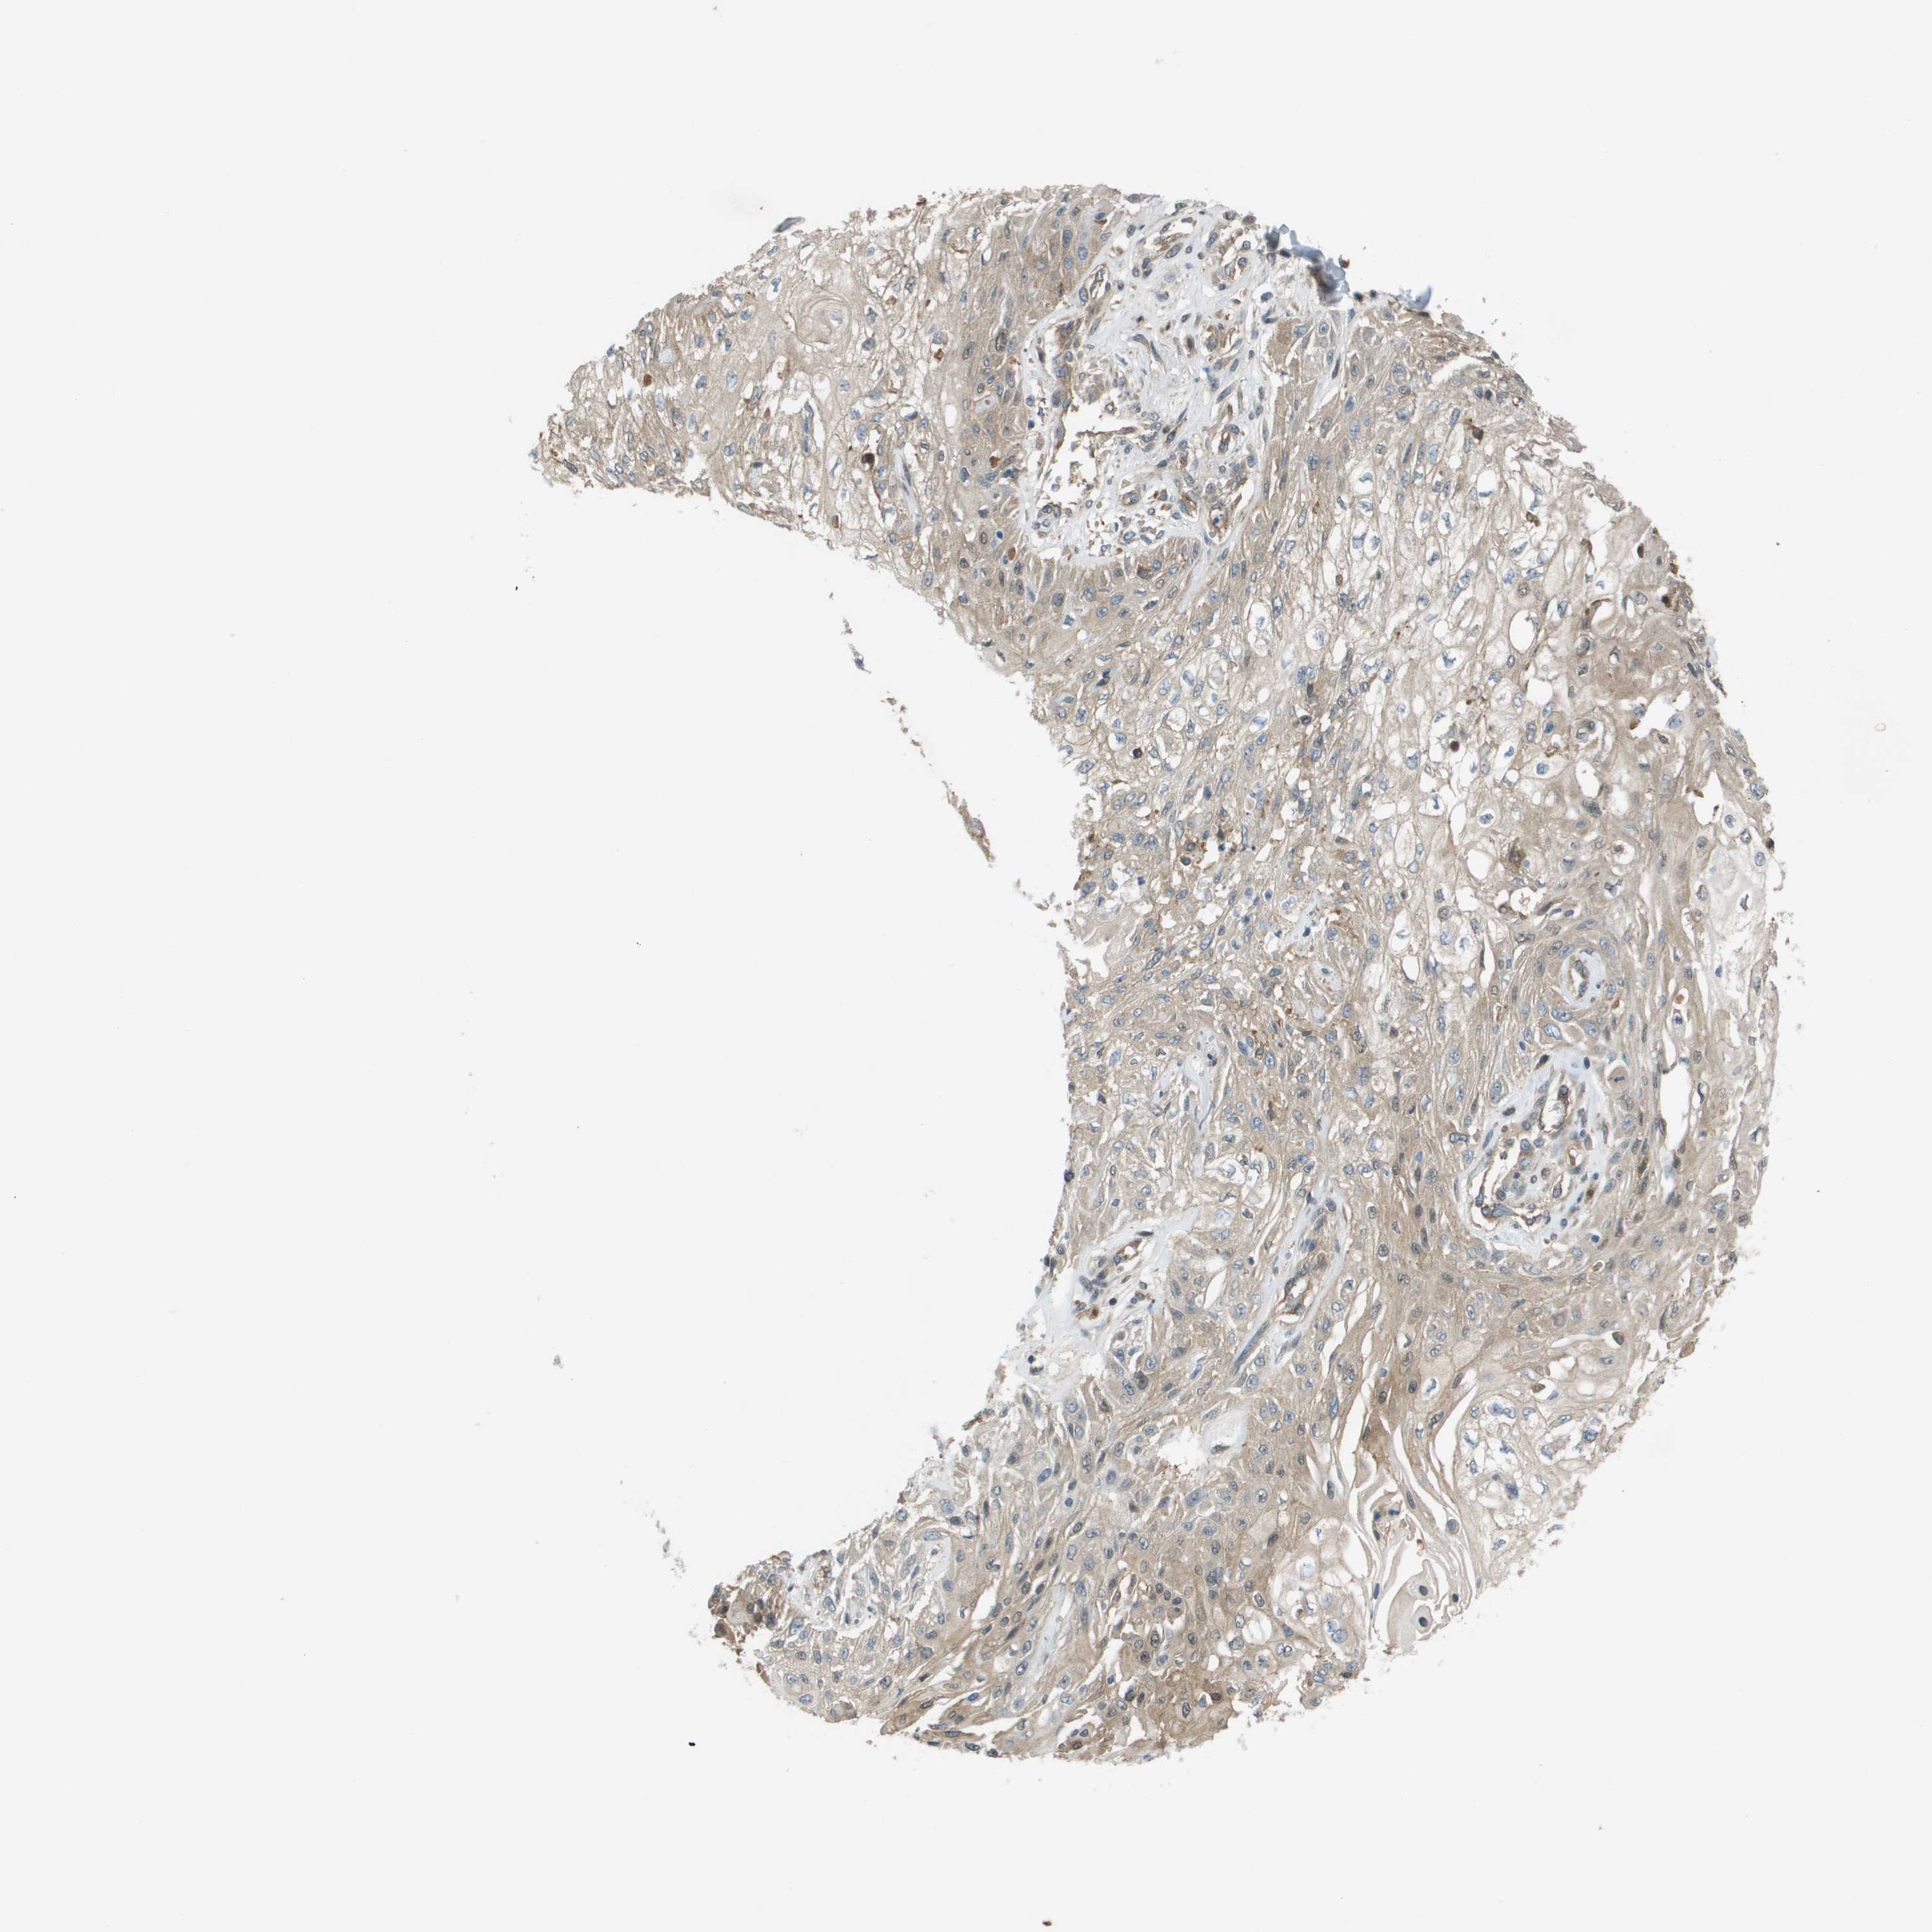

SKIN CANCER - Protein expressioni

A mouse-over function shows sample information and annotation data. Click on an image to view it in a full screen mode. Samples can be filtered based on level of antibody staining by selecting one or several of the following categories: high, medium, low and not detected. The assay and annotation is described here.

Antibody stainingi

Antibody staining in the annotated cell types in the current human tissue is reported as not detected, low, medium, or high, based on conventional immunohistochemistry profiling in selected tissues. This score is based on the combination of the staining intensity and fraction of stained cells.

Each image is clickable and will lead to virtual microscopy that enables deeper exploration of all samples and also displays staining intensity scores, fraction scores and subcellular localization as well as patient and tissue information for each sample.

Antibody HPA070456

Antibody CAB017616

Staining

High

Medium

Low

Not detected

Intensity

Strong

Moderate

Weak

Negative

Quantity

>75%

75%-25%

<25%

None

Location

Nuclear

Cytoplasmic/membranous

Cytoplasmic/membranous,nuclear

Basal cell carcinoma

Squamous cell carcinoma, NOS

Squamous cell carcinoma in situ, NOS

Adnexal tumor, benign